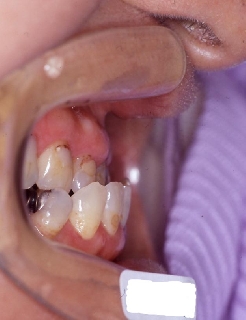

インプラント治療の為の矯正治療症例1

初診時年齢58歳。下顎臼歯部インプラント治療前の咬合改善を目的に来院。

咬み合わせを高くする事で受け口の改善ならびに下顎インプラント挿入スペースを作成した。

矯正治療と並行して専門医によるインプラント治療を行った。